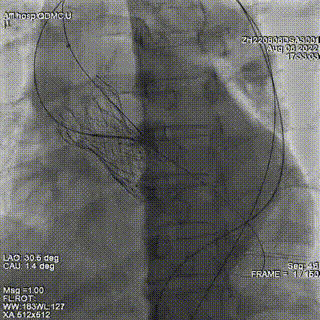

根据造影确定瓣周漏位置,在第一个封堵器旁探查,再次通过瓣周漏,置换鞘管后置入第2枚封堵器,仍选择6mmADOII。封堵器释放后位置良好。

超声提示2枚封堵器位置良好,瓣周反流明显减少,但仍有少-中量瓣周反流。遂在已植入封堵器旁再次探查,并通过瓣周漏。因交换鞘管困难,遂采用LOOP法建立轨道,引导输送鞘管通过瓣周漏。